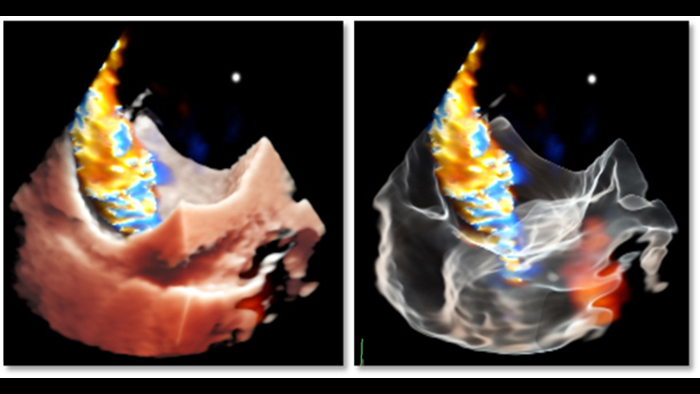

Información detallada con TrueVue color y GlassVue

Representación fotorrealista de TrueVue cardiaco con alineación de imagen de MultiVue